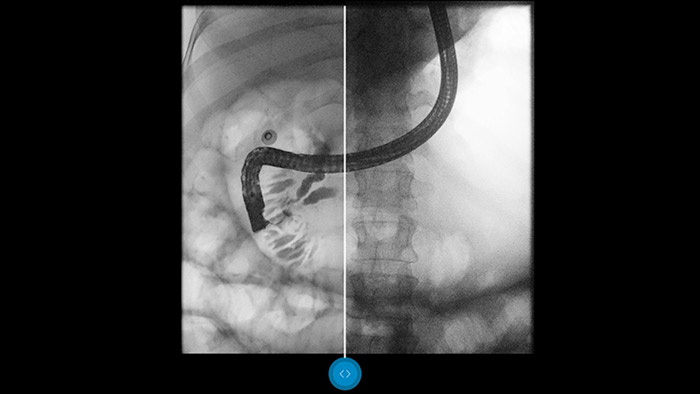

Compárelo con un procesador de imágenes convencional para ver los beneficios usted mismo.

El software de procesamiento de imágenes Dynamic UNIQUE equilibra el contraste. Además, realza los detalles más débiles y brinda una calidad de imagen uniforme, lo cual permite distinguir claramente los huesos de los tejidos blandos.

Dynamic UNIQUE ofrece una excelente visibilidad de los detalles con supresión del ruido en tiempo real, desde el primer fotograma hasta el último. La información de diagnóstico para cada fotograma se muestra con gran claridad, con el brillo correcto y con una latencia muy baja. La representación de la imagen es coherente y estable, incluso cuando el contenido de la imagen varía rápidamente. Dynamic UNIQUE admite exámenes rápidos y seguros con dosis bajas al proporcionar claridad de detalle para mejorar su confianza en el diagnóstico.